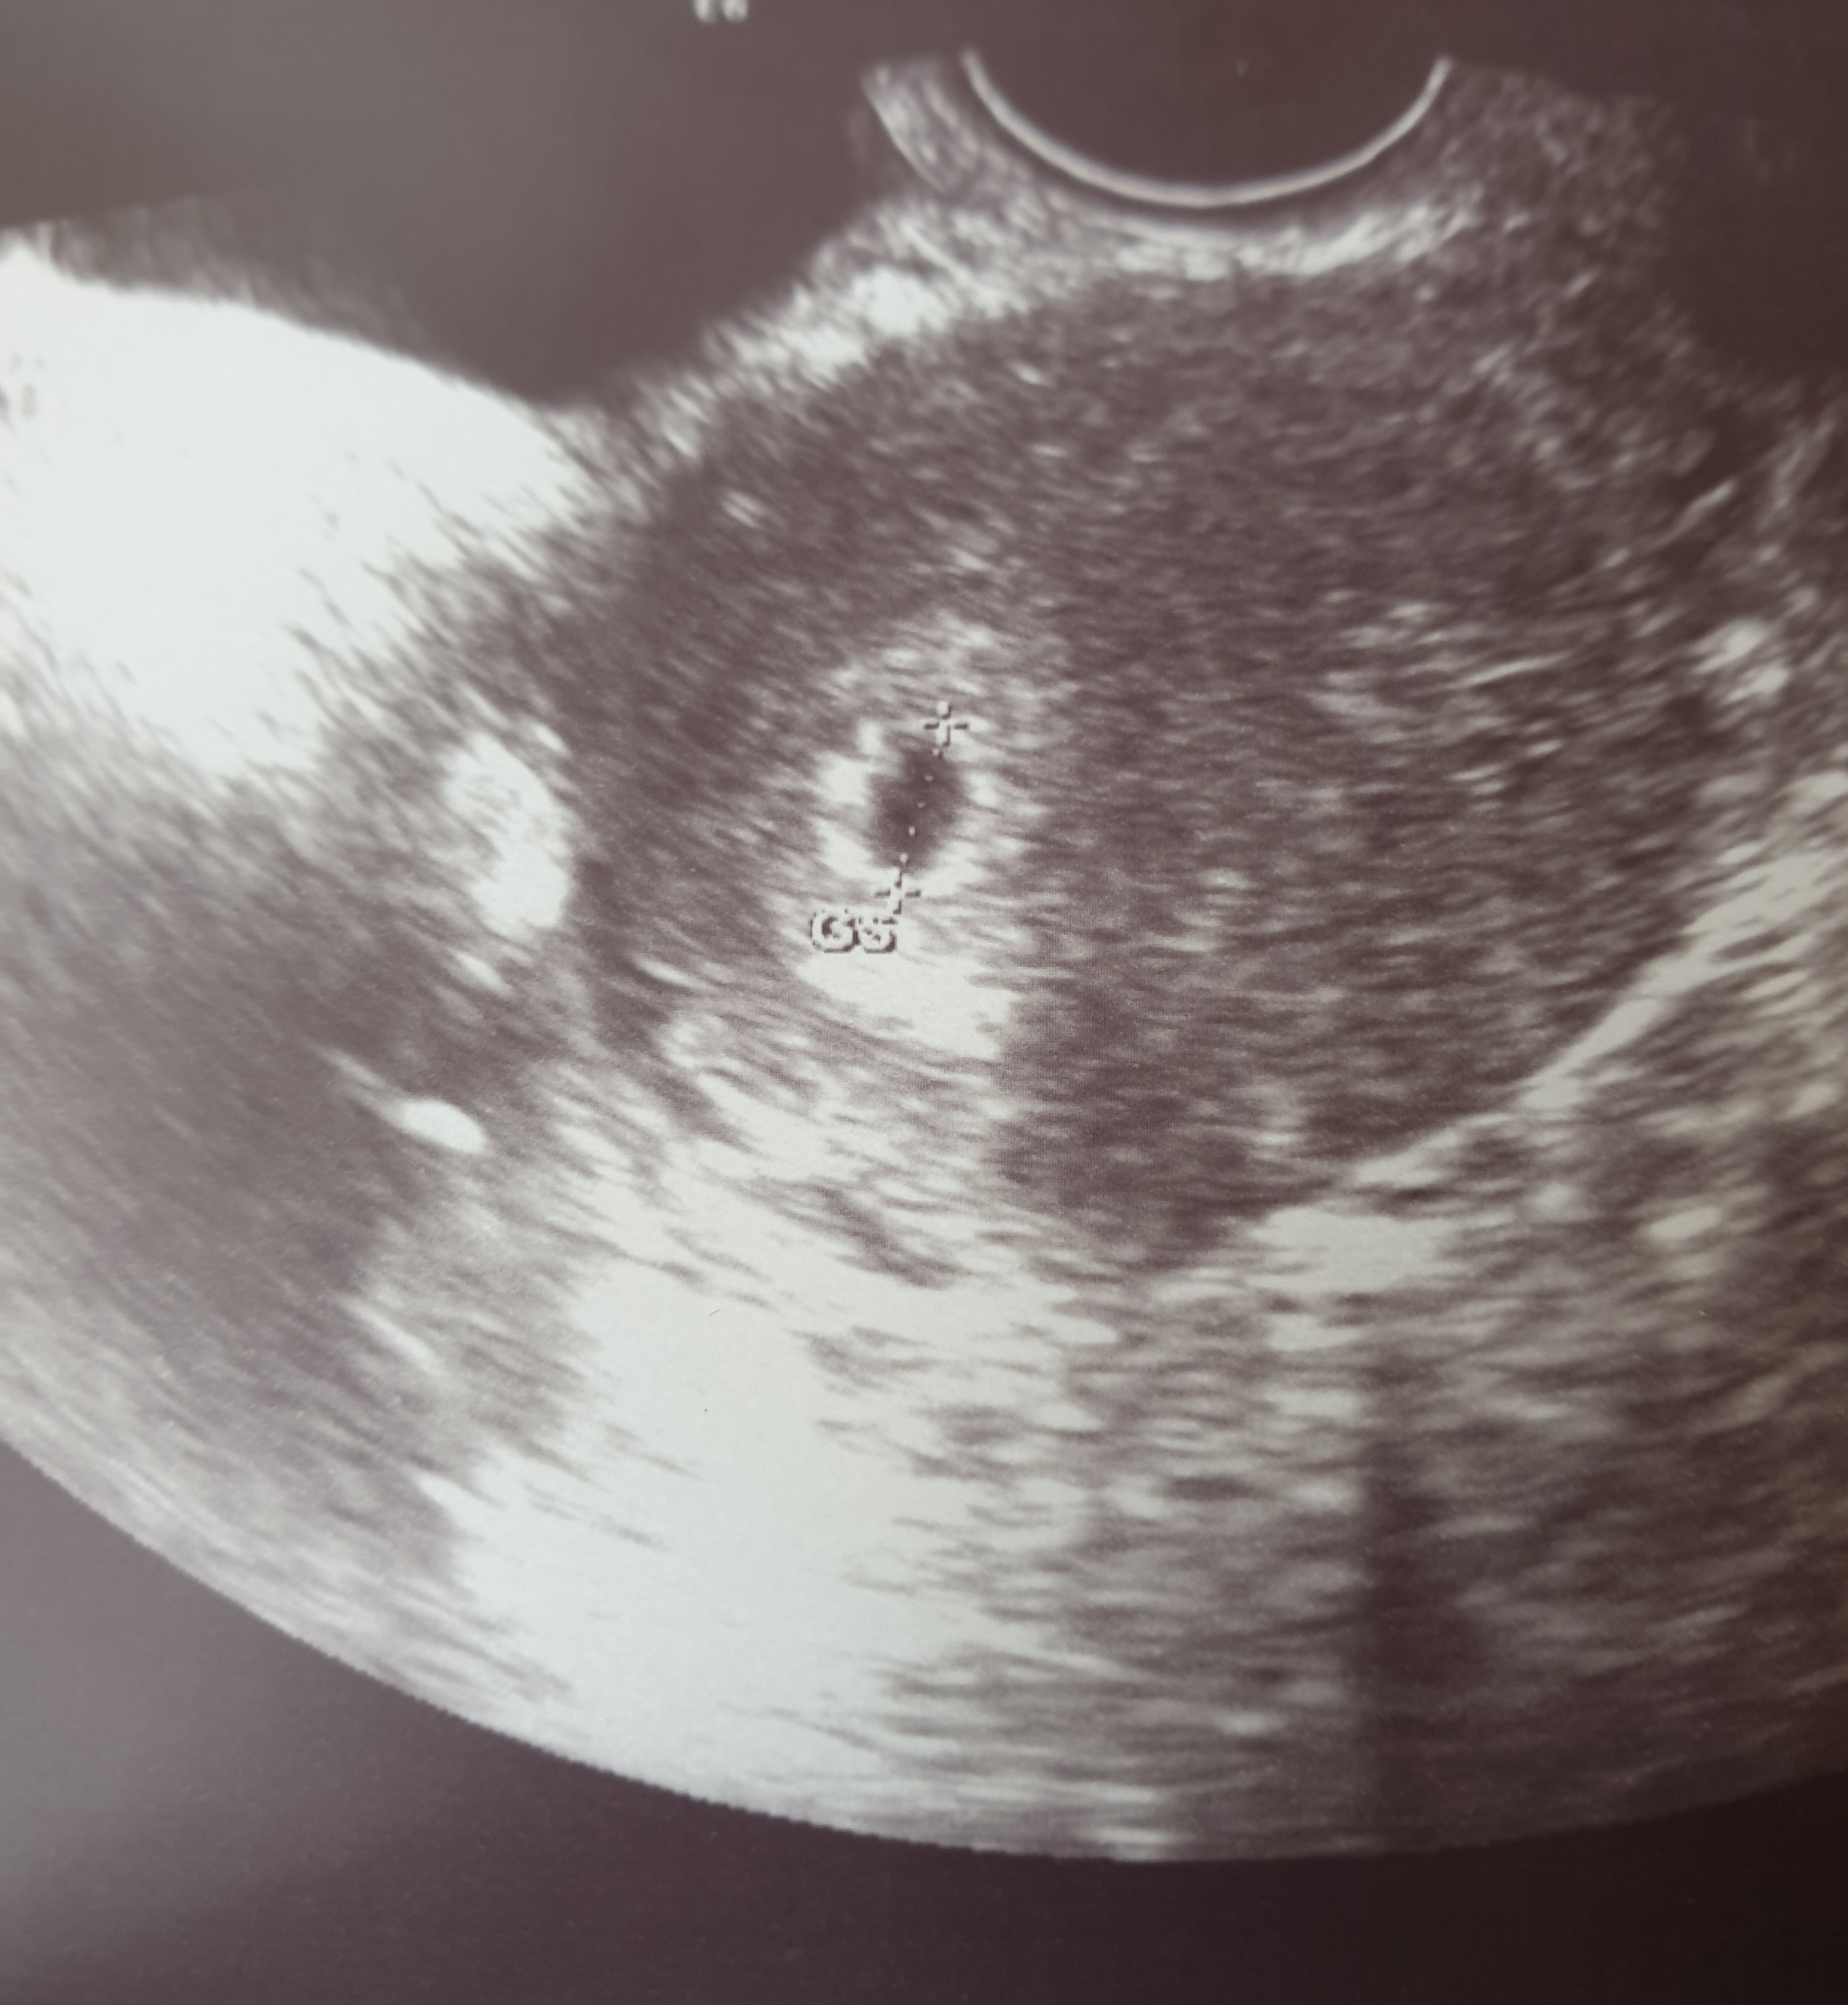

Lekarz mówi, że jest dobrze. Pęcherzyk ciążowy 7mm .Zobacz załącznik 1141870